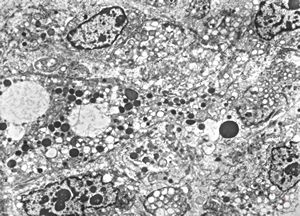

M,54y. | Whipple disease

Whipple disease